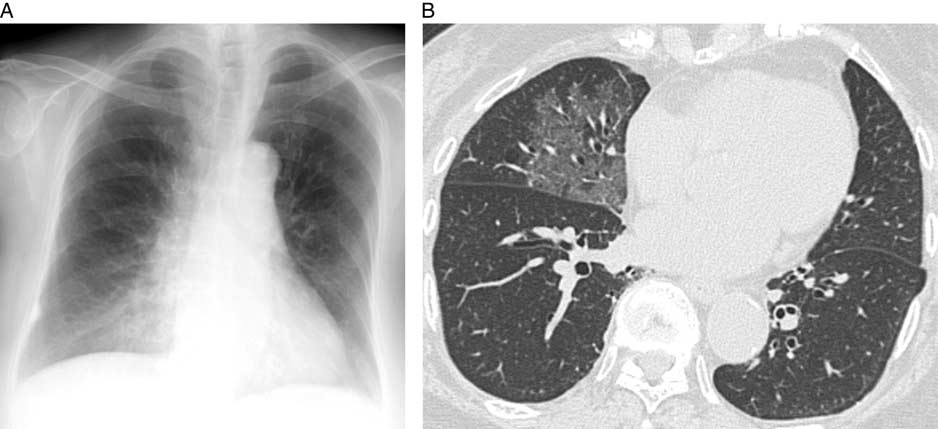

辅助检查:常规实验室检查各项指标均在正常范围内。初诊时胸片显示右下肺透明度降低,CT肺窗示右中叶的磨玻璃影(GGO),胸膜下区保留(图1)。CT软组织窗示GGO内未见脂肪衰减。

图1 初次时的胸部成像。A.胸片显示右下肺透明度降低;B.CT肺窗示右中叶GGO,胸膜下区保留。